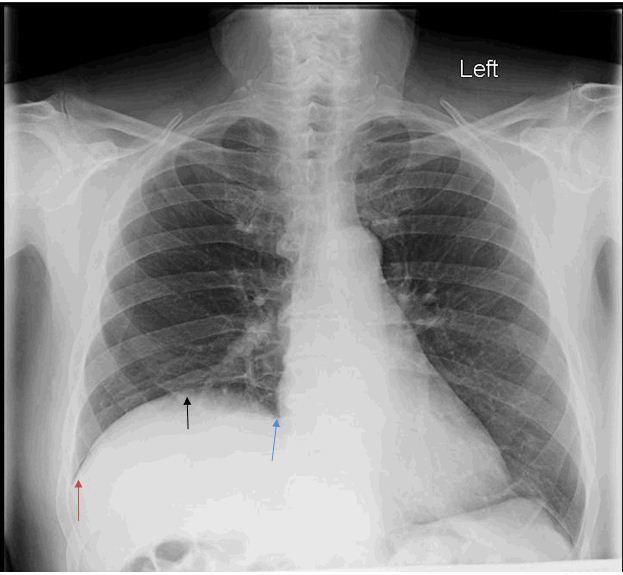

Pneumoperitoneum and subphrenic abscess are two important differential diagnosis of this radiographic sign which can be excluded out when normal plicae circulares or haustral markings of the colon is seen under the right diaphragm. If youre experiencing mild discomfort in your diaphragm take a few minutes to concentrate on deep breathing. Treatment depends on the type of hiatal hernia you have and on your symptoms.

Place one hand on your abdomen and breathe deeply. Reduced number of alveoli air sacs required for normal breathing. In severe cases when there is no simple treatment that can relieve dyspnea your doctor may prescribe morphine. Congenital diaphragmatic hernia CDH. There is usually a long history of heavy smoking. Shortness of breath may be accompanied by wheezing. Diaphragmatic dysfunction caused by transverse myelitis or leukemic infiltration of the cervical spinal cord in a patient with leukemia and shortness of breath. To treat phrenic nerve irritation This condition can be managed with a breathing pacemaker which takes over the responsibility of sending messages to the diaphragm. The cause for shortness of breath was thought primarily due to stable angina on tread mill test positive finding but Chilaiditis syndrome should also be considered as a cause for the shortness of breath.